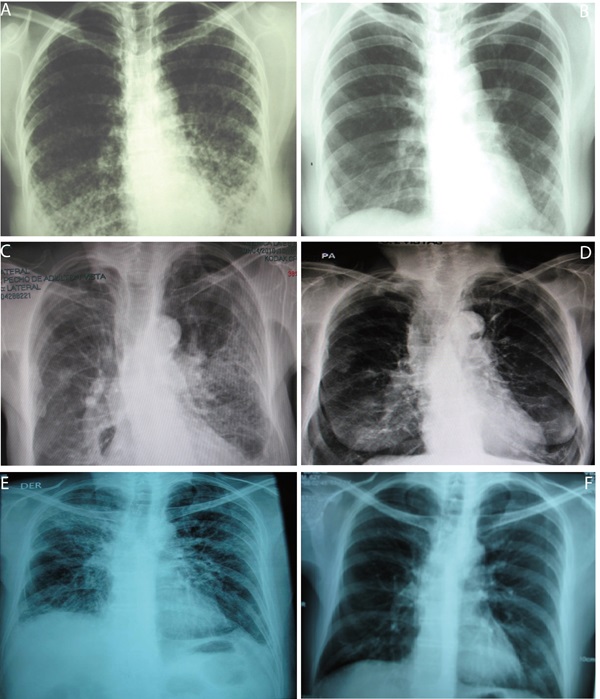

A 38 year-old woman, heterosexual with no history of promiscuity, was admitted to a medical care hospital on January 21th, 2002 with a 3 month history of chills, fever and coughing with sputum production, progressive dyspnea, fatigue, weakness, anorexia and 10 kg weight loss. At the time of presentation she was being treated with 4 antituberculosis drugs for 34 days determined by bilateral reticulonodular interstitial infiltrates in her chest X-ray (Fig. 1A) and chest computed tomography (chest CT). Samples of bronchoalveolar lavage (BAL) were mycobacteria stain and culture negative. Transtracheal wash was fungus stain and culture negative too. She had a low level of hemoglobin (11.3 g/dL), hematocrit (37.7%), peripheral blood lymphocytes (699 /mm3), CD4+ T cells/mm3 92 (13.2%) and CD8+ T cells/mm3 144 (Table 1 and Figure 2:A-C). Lung biopsy showed nonspecific focal, interstitial fibrosis, a few Pneumocystis jiroveci (P. jiroveci) and DNA of EBV by polymerase chain reaction (PCR). The patient's vital signs showed a temperature that ranged from 38 °C to 39.5 °C, respiratory rate of 40, pulse of 140, weight of 43 kg, height 1.62 m. Treatment with trimethoprin sulfamethoxazole and prednisone for 21 days was commenced on February 6th. The patient's temperature fell to 38 °C and pulse to 128, but she persisted tachypneic with a respiratory rate of 56 and coughing. Her weight decreased to 38 kg.

The result of serum antibodies of different viruses included CMV, EBV and HIV test are shown in Table 1. On April 16th, 2002, treatment with intravenous ganciclovir and 80,000U of interferon α sublingual every 8 h was commenced. Five days later her vital signs had improved with a respiratory rate of 36, pulse of 88 and weigh of 42 kg. One month after ganciclovir was commenced the lymphocytes count had risen to 3,148/mm3 and CD4+ T cells count was 322 cells/mm3 (10.2%) and CD8+ T cells count was 228 cells/mm3 (Fig. 2:A-C). She was treated with ganciclovir for 5 months and INFα for 8 months. In June 2003, her weight was 60 kg, respiratory rate 20, pulse 80 and her chest X-ray had only minimum residual lesions in the lower lung lobes (Fig. 1B). On October 14th, 2010 the patient was asymptomatic and her lymphocytes count was 1,988/mm3, CD4+ T cells were 503/mm3 (25.3%), with 684 CD8+ T cells/mm3. Also her CD4+/CD8+ T cells ratio was normal (Fig. 2: A-D).

A 74 year-old woman with history of osteoporosis, gastric cancer 30 years before, cigarette smoke exposure, chronic obstructive pulmonary disease with spontaneous pneumothorax 8 months before, was attended by Staphylococcus aureus methicillin sensitive bacteremia and pneumonia. She was treated since April 1st, 2010 with piperacillin-tazobactam and mechanical ventilation support. The hemograms of April 1st and 9th showed lymphocytopenia of 610 mm3 and 450 mm3 respectively. A chest CT showed findings of pulmonary thromboembolism, alveolar infiltrates in the left lung and interstitial fibrotic lesions, bulla, bilateral pleural effusion and right cardiomegaly (Fig. 1 C). On April 11th, she had 109 CD4+ T cells/mm3 (17.9%) and 43 CD8+ T cells/mm3 (Fig. 2: A-C). On April 9th she was treated with trimethoprin sulfamethoxazole for Stenotrophomonas maltophlia nosocomial pneumonia and empirical for P. jiroveci pneumonia. Predisone plus ganciclovir were added. The results of antibodies to different virus are in Table 1. On April 27th, her lymphocytes count increased to 730/mm3. On April 30th, she could be removed from mechanical ventilatory support. She was treated with valganciclovir for 3 months and voriconazole for 4 months, by repeated isolation of Aspergillus fumigatus in bronchial secretions without a lung biopsy because of the high risk of the procedure. In August she had an improvement in her immunology alterations which are shown in Table 1 and Figure 2: A-D. She also improved pulmonary infiltrates (Fig. 1: D).

A 62 year-old professor was diagnosed on November 7th, 2010 with coughing, adynamia, fatigue and progressive dyspnea for four months before. He had antecedents of amigdalectomy at 19 years old, hepatitis at 16 years old, appendectomy at 59 years old, red blood cells transfusion during diverticulitis with peritonitis in January 2006 and chronic renal diseases treated with hemodialysis until May 2007. Also he had a history of oral ulcers on two occasions in 2008 and urinary infection in January 2009. At the moment of medical examination, his chest X-ray showed diffuse bilateral interstitial infiltrates (Fig. 1E). The chest CT had reticular infiltrates greater in the right upper lung lobule, bronchiectasis, irregular interstitial subpleural thickening and ground-glass opacities superimposed. Previously, he had tuberculin test on 11 mm but the ZN smear mycobacterial and fungus culture of BAL and three ZN sputum were negative.

On November 17th, 2009, the lymphocytes count was 681/mm3, CD4+ T cells were 279 / mm3 (40.9%) and CD8+ T cells were 110/mm3 (Table 1 and Fig. 2: A-C). He had IgG and IgM anti CMV negative but CMV PP65 antigen positive Table 1. On November 22th, 2009 a induced sputum calcofluor stain showed structures compatible with P. jiroveci. On November 23rd, he was treated with prednisone and trimethoprin-sulfamethoxazole for 3 days followed by clindamycin and primaquine for 18 days. On November 26th, he started ganciclovir for 3 months. On December 17th the fever, cough, dyspnea, fatigue and weight loss had improved. On December 17th, 2009 the lymphocytes count was 957/mm3, CD4+ T cells were 318/mm3 (33.2%) and CD8+ T cells were 182/mm3. The improvement of different immunology alterations, after gancicolvir treatment, can be seen in Table 1 and Fig.2:A-D. The radiology pulmonary infiltrates improvement can be seen in the Fig.1: F.